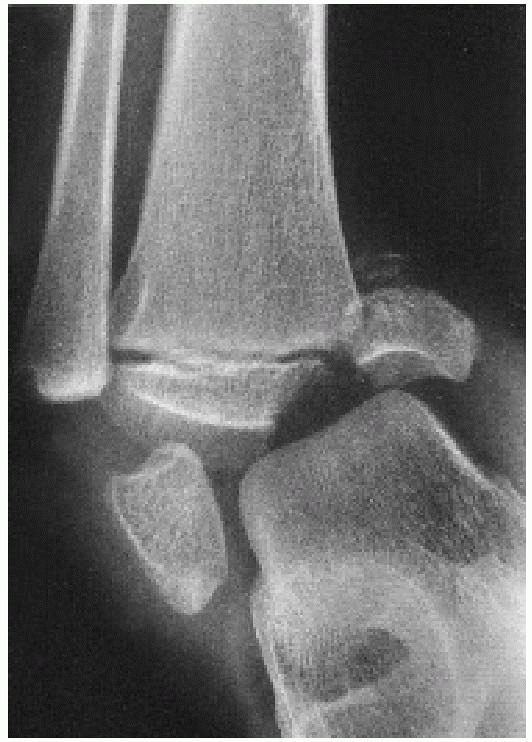

![]() |

FIGURE 26-2

Comminuted Salter-Harris type IV fracture of the distal tibia and displaced Salter-Harris type I fracture of the distal fibula produced by an inversion (shearing) mechanism in a 10-year-old girl. |

-

Grade I: The adduction or inversion force

avulses the distal fibular epiphysis (Salter-Harris type I or II

fracture). Occasionally, the fracture is transepiphyseal; rarely, the

lateral ligaments fail. -

Grade II (Fig. 26-4):

Further inversion produces a tibial fracture, usually a Salter-Harris

type III or IV and rarely a Salter-Harris type I or II injury, or the

fracture passes through the medial malleolus below the physis (Fig. 26-5).